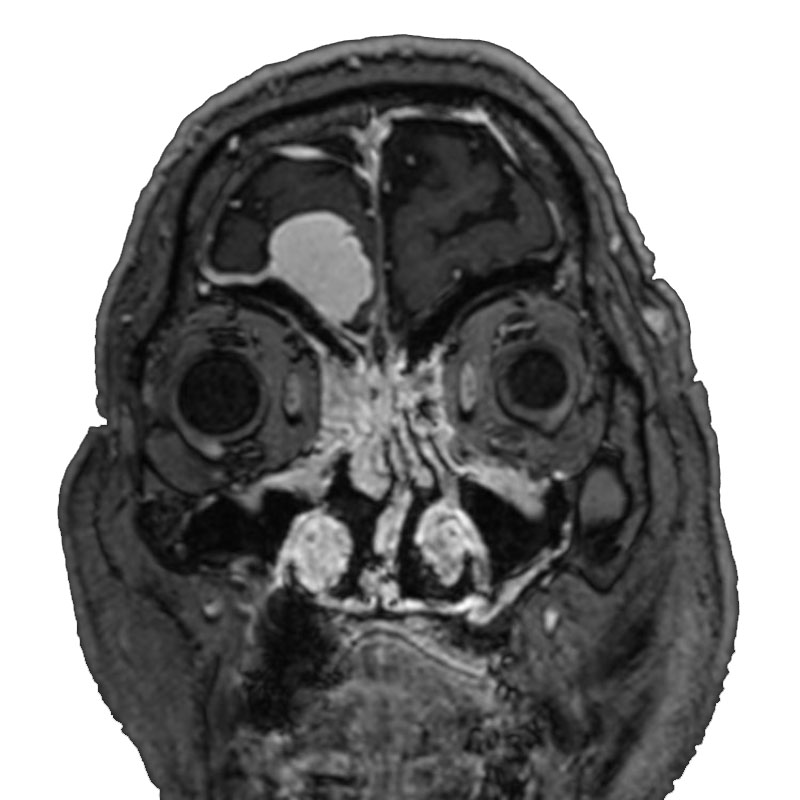

脳動静脈奇形

摘出術

南田/野本/古谷/元永